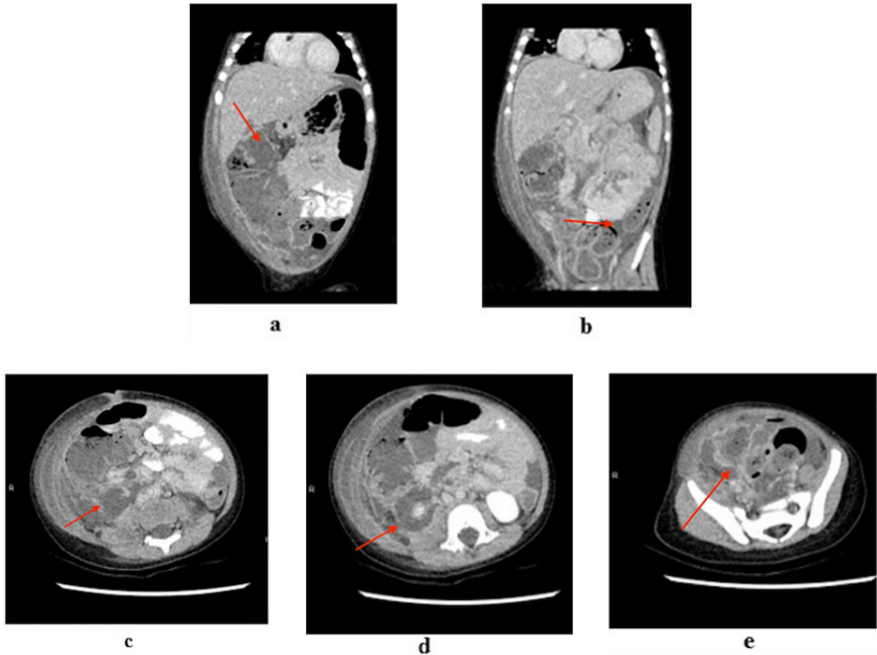

腹部超声检查无法定位任何病变,包括肾盂肾炎(图1)。腹部和骨盆的CT显示大量腹水,腹膜向腹盆交界处呈斑片状强化。大肠内可见低密度液体;升结肠扩张伴肠积气,可能存在肠缺血。在腹盆交界处发现一个长方形边缘强化集合。还有中等量的右侧肾周积液(图2)。

图2. 腹部CT和骨盆造影图像。(a)整个大肠的低密度液体;扩张的升结肠伴有肠积气;(b) 大量腹水,腹膜向腹盆交界处呈片状强化;(c) - (d) 中等容量的右侧肾周积液; (e) 腹盆交界处的椭圆形边缘增强集合